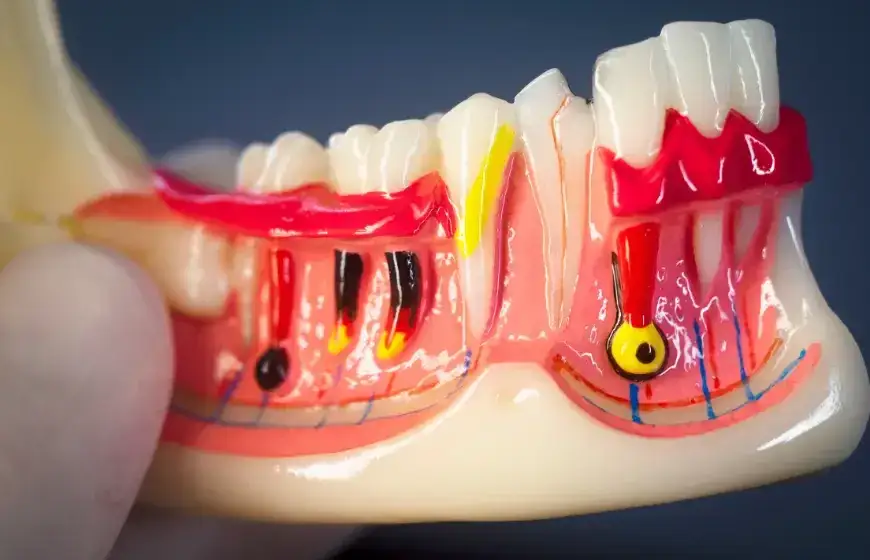

Zgorzel zęba to nic innego jak gnilny rozpad miazgi zęba, czyli jego wewnętrznej, żywej tkanki, w której znajdują się naczynia krwionośne i nerwy. Ten proces jest wywołany przez bakterie beztlenowe, które dostają się do wnętrza zęba. Najczęściej winowajcą jest głęboka, nieleczona próchnica, która otwiera bakteriom drogę do miazgi. Czasem przyczyną mogą być również urazy mechaniczne, takie jak złamania czy pęknięcia zęba, lub uszkodzenia termiczne. Dlaczego zgorzel tak bardzo boli? Głównym powodem jest gromadzenie się gazów gnilnych w zamkniętej przestrzeni zęba. Wzrost ciśnienia wewnątrz zęba, połączony ze stanem zapalnym otaczających tkanek, wywołuje ten nieznośny, rozpierający ból, który często opisują moi pacjenci.

W stomatologii rozróżniamy dwa typy zgorzeli, które mają wpływ na intensywność odczuwanego bólu. Mamy do czynienia ze zgorzelą "zamkniętą", gdy gazy gnilne gromadzą się w szczelnej komorze zęba. Wtedy ból jest wyjątkowo silny i rozpierający, ponieważ ciśnienie wewnątrz zęba rośnie. Natomiast przy zgorzeli "otwartej", kiedy jest ubytek (np. duża dziura w zębie), przez który gazy mogą się ulatniać, ból może być znacznie mniejszy lub nawet nie występować. W tym drugim przypadku głównym objawem jest często nieprzyjemny zapach z ust, który jest efektem uwalniania się produktów rozpadu.